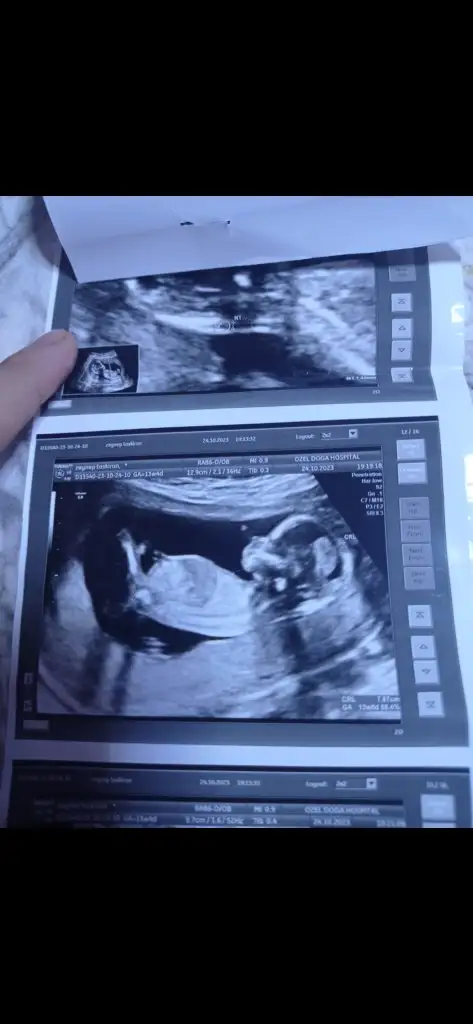

Benimkine de bakabilir misiniz doktorum 11+5te kız dedi 13+6da erkek dedi

İlk 3 fotoğraf 13+6

Son 2 fotoğraf 11+5